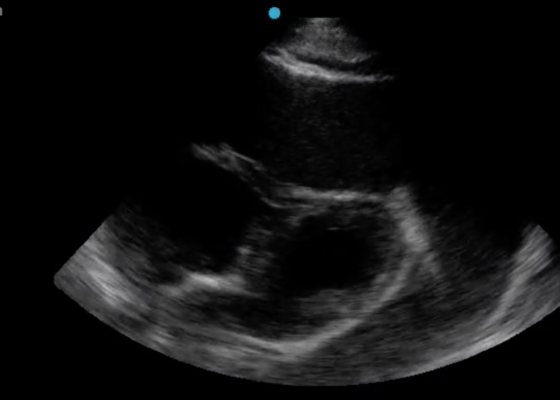

A Case Report of Cardiac Tamponade

DOI: https://doi.org/10.21980/J8J644The patient was in noticeable respiratory distress and had oxygen saturation of 94% on room air. Bilateral jugular venous distention with severe right supraclavicular lymphadenopathy and diffuse bilateral wheezing was present. Although muffled heart sounds and hypotension are part of Beck’s Triad, these were not present in this case. Electrocardiogram obtained on arrival showed a sinus tachycardia with low-voltage QRS complexes and electrical alternans. Low voltage QRS can be seen on the ECG provided and is demonstrated by the low amplitude of the QRS complexes seen on all the leads. Electrical alternans may have an alternating axis or amplitudes of the QRS complex. Alternating axis is best visualized in V4-V6 on this ECG while alternating amplitudes are seen throughout the rest of the ECG. Computed tomography angiogram (CTA) of the chest revealed a large pericardial effusion with bilateral pulmonary emboli and a right upper lobe mass. A bedside transthoracic echocardiogram (TTE) was then performed and confirmed the large effusion, but also showed right ventricular collapse during diastole, indicative of cardiac tamponade.